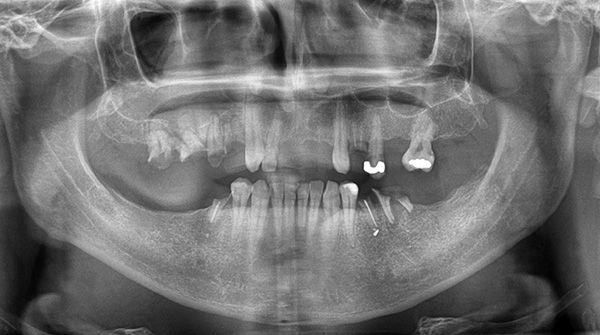

Atualmente, essa complicação de implantação é muito menos comum do que antes. O progresso ocorreu em grande parte devido à capacidade de determinar com precisão a distância das massas abdominais usando imagens panorâmicas e tomografia computadorizada (TC).

Para reduzir o risco dessa complicação para quase zero, você precisa confiar apenas em um médico experiente com um longo histórico de trabalho e, em caso de dúvida - consulte outros implantologistas. No caso de uma localização próxima do seio maxilar e do fundo da cavidade nasal, um “acúmulo" do osso (elevação do seio) pode ser realizado anteriormente e, portanto, não há problemas.

A foto abaixo mostra um exemplo de extensão do tecido ósseo antes da implantação do dente: